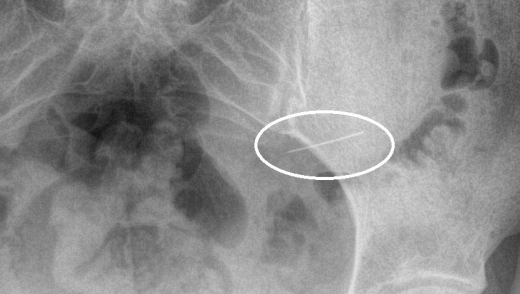

Жительница Красногорска случайно проглотила швейную иглу — она сразу обратилась за медицинской помощью, что позволило избежать серьезных осложнений, сообщает Минздрав Подмосковья. Детали произошедшего не уточняются. К моменту поступления в больницу игла была в желудке. Опасный предмет был благополучно удален с помощью эндоскопического оборудования. «Если бы игла задержалась в организме на более долгий срок, это могло бы повлечь за собой серьезные осложнения, такие как перфорация стенок желудка или кишечника, кровотечение, перитонит и даже сепсис», — сказал заведующий первым хирургическим отделением Николай Мурашов. Специалисты напоминают, что если вы все же случайно проглотили инородное тело, то не стоит пытаться вызвать рвоту или принять какие-либо другие меры самостоятельно. Ранее в той же больнице спасли женщину, которая наглоталась швейных иголок. У нее обнаружили три иглы в брюшной полости и одну — в передней брюшной стенке. Одна из них прошла через стенку желудка и даже проникла в поджелудочную железу. Выяснилось, что женщина проглотила иглы почти за месяц до этого. За это время они успели обрасти тканями.